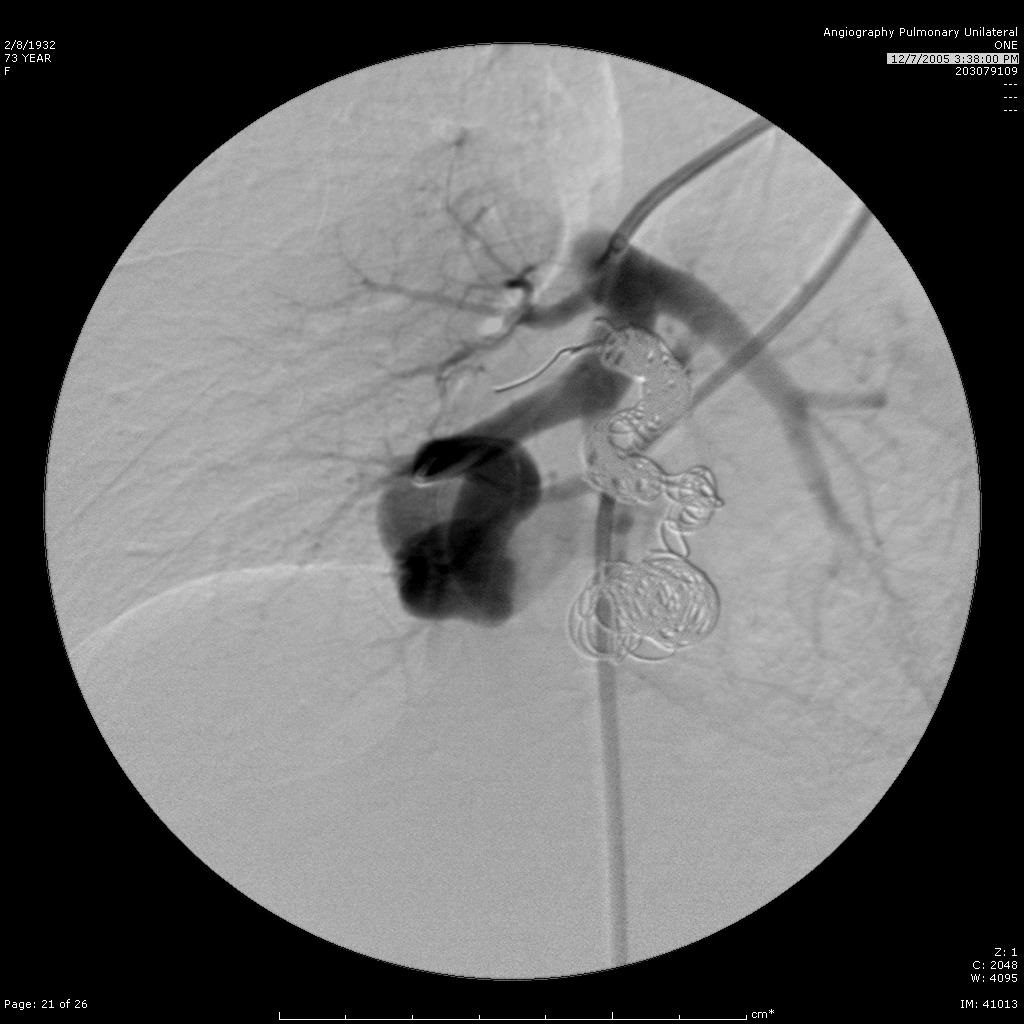

栓塞后弹簧栓子逸出至右肺静脉 |

弹簧栓子在左心房“狂”跳 |

去哪儿啦? |

在这儿! |

嵌在股深浅动脉分叉处 |

弹簧栓子被移除 |

继续栓塞 |

研究静脉池出口情况 |

寻找最佳工作位 |

静脉池出口直径大 |

放弃静脉池栓塞,仅栓塞滋养动脉 |

完成任务 |